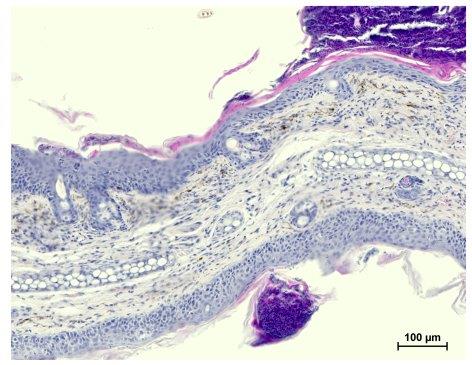

Expression of a pathogenic human CARD14 mutant transgene in keratinocytes is sufficient to drive psoriasis‐like dermatitis in mice (Van Nuffel et al., EMBO Rep. 2020)